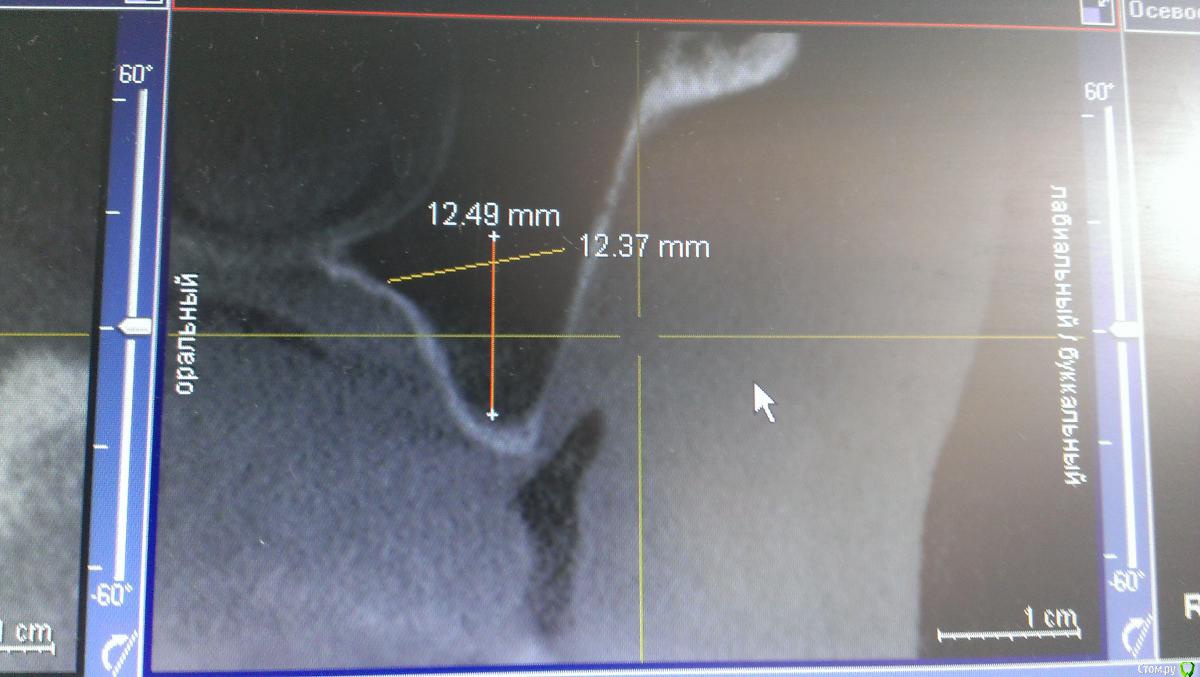

AlexFox Опубликовано 13 июля, 2016 Поделиться Опубликовано 13 июля, 2016 Доброго времени суток,коллеги.Огромная просьба к имплантологам поделиться своим мнением по-поводу клинического случая.Пациенту 45 лет,жалобы на отсутствие жевательной группы зубов во втором сегменте.Для постановки имплантов требуется синуслифтинг.Меня настораживает малый объем имеющейся костной ткани при большом объеме поднятия дна.Плюс слизистой на кт я вообще не вижу.Хотелось бы узнать ваше мнение об этом. Ссылка на комментарий

BugDan Опубликовано 14 июля, 2016 Поделиться Опубликовано 14 июля, 2016 (изменено) Я бы сделал синус с ауто-ксено 1:1 по причине чистой кортикалки в области моляров.Ставить ли импланты сразу или нет зависит от макродизайна имплантатов котрыми вы планируете пользоваться и опыта в первую очередь.На картинках планирования 23 стоит далековато от 22 , винт 5 стоит чуть медиальнее чем надо, а 6 сильно медиальнее чем нужно. Для страховки просмотрите латеральную стенку синуса на предмет артерии. Изменено 14 июля, 2016 пользователем BugDan Ссылка на комментарий